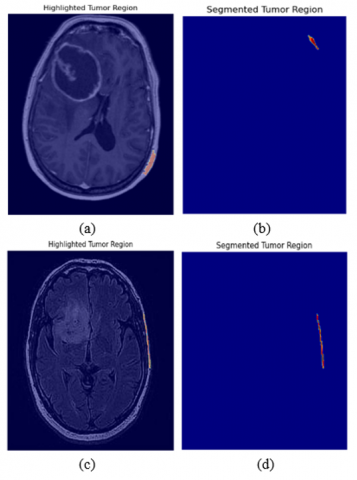

Figure 11. Results of graph-based algorithm for segmentation

Figure 11 shows the successful segmentation results where the algorithm accurately highlighted the tumor region, achieving near-perfect delineation of the tumor boundaries. To further understand the limitations of the technique, Figure 12 consists of MRI images where the technique failed to highlight and segment the tumor region.

Images on which the segmentation performed poorly are shown below where the technique fails to highlight the tumor region.